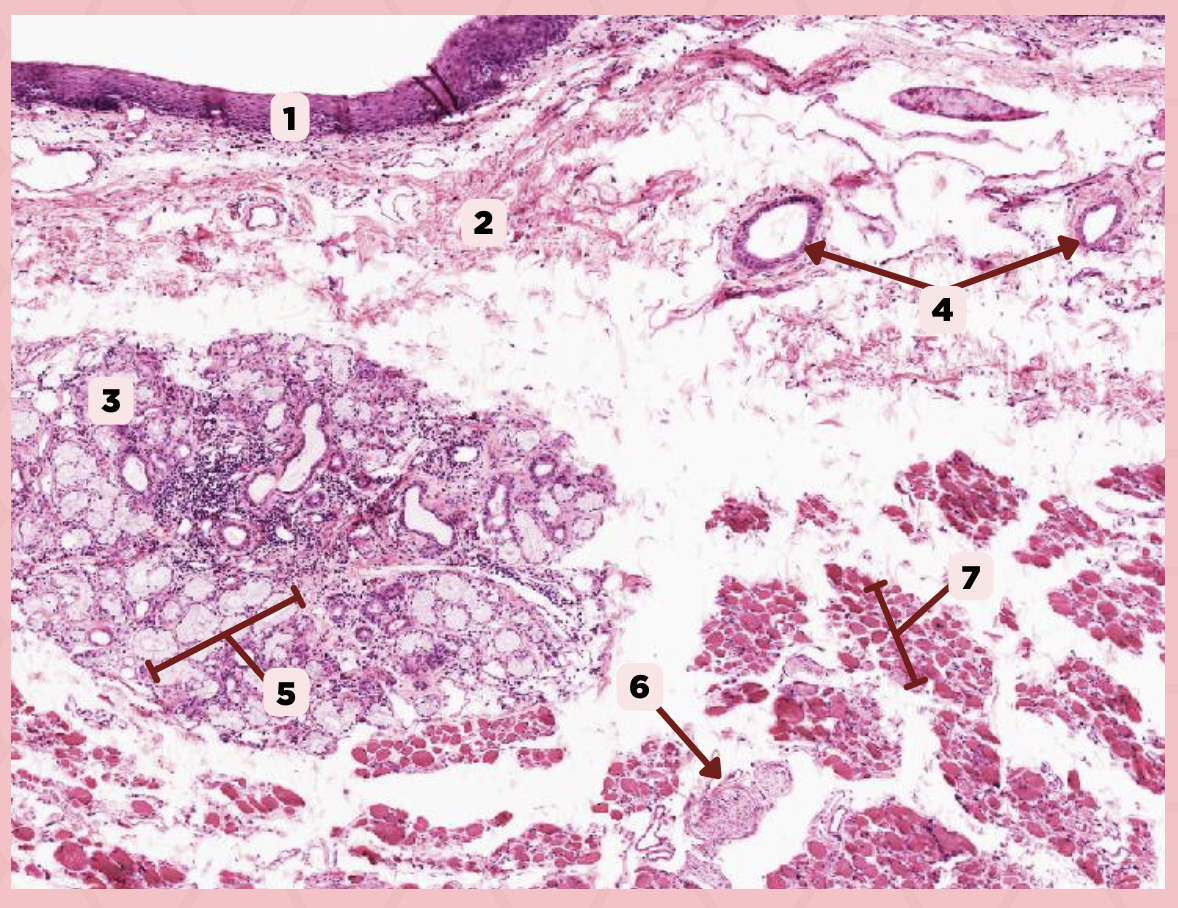

Lip

What is the specimen showed in the picture?

Epidermis

Identify the structure labeled as 1.

Dermis

Identify the structure labeled as 2.

Arrector Pilli Muscle

Identify the structure labeled as 3.

Hair Follicle

Identify the structure labeled as 4.

Sebaceous Glands

Identify the structure labeled as 5.

Lip

What specimen is showed in the picture?

Labial Glands (in the Mucosa)

Identify the structure labeled as 1.

Skeletal Muscle Cells

Identify the structure labeled as 2.

Lamina Propria

Identify the structure labeled as 3.

Mucosa

Identify the structure labeled as 4.

Lip

What specimen is showed in the picture?

Skeletal Muscle Fibers

Identify the structure labeled as 1.

Labial Glands

Identify the structure labeled as 2.

Cheek

Identify the specimen.

Mucosa

Identify the structure labeled as 1.

Lamina Propria

Identify the structure labeled as 2.

MALT

Identify the structure labeled as 3.

Blood Vessels

Identify the structure labeled as 4.

Buccal Glands

Identify the structure labeled as 5.

Nerve

Identify the structure labeled as 6.

Muscle Fascicles

Identify the structure labeled as 7.